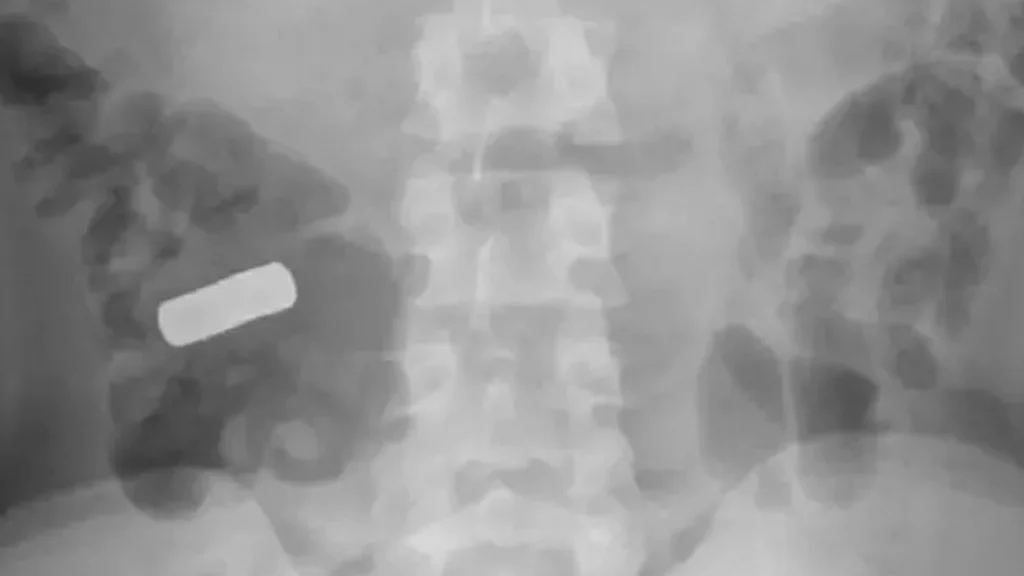

Foto: BMJ Case Reports

Da en 21-årig mand blev overvældet af smerte i sin mave, besluttede han at opsøge et hospital. CT- og røntgenscanninger afslørede årsagen til hans voldsomme mavesmerter: en række metalstykker i maven.

Denne mystiske sag, beskrevet i en artikel i BMJ Case Reports, bliver endnu mere forunderlig, da teenageren ikke selv kan erindre at have indtaget de 21 magneter, som scanningerne afslørede.